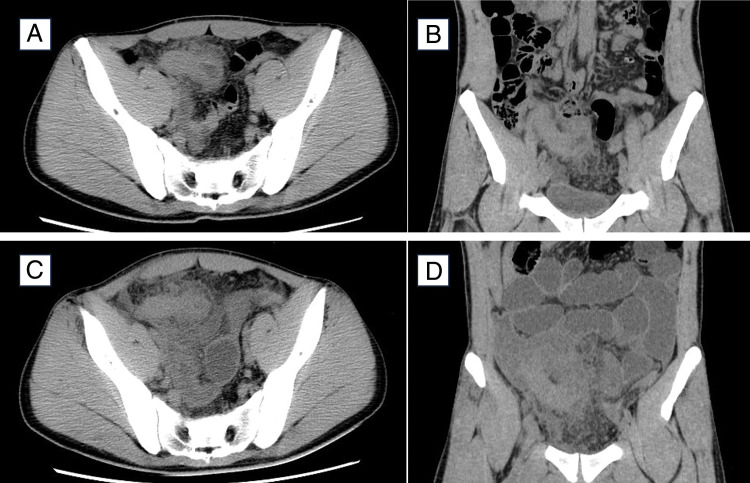

Case presentation: A 21-year-old man underwent open appendectomy after antibiotic treatment for acute appendicitis proved ineffective. Postoperative pathological findings confirmed acute appendicitis. Antibiotics were continued after surgery, and the patient's fever and abdominal symptoms gradually improved. However, abdominal distension recurred on the 18th day of hospitalization. Blood tests showed a re-elevation of the white blood cell count, suggesting a postoperative intraperitoneal abscess. Despite further antibiotic treatment, fever and leukocytosis persisted. On the 28th day of hospitalization, abnormal lymphocytes were detected in the peripheral blood, and we realized that the persistent fever was due to systemic symptoms of malignant lymphoma rather than a complication of appendicitis. On the 30th day, the patient was referred to the hematology department and subsequently diagnosed with Burkitt lymphoma. Chemotherapy was initiated on the 40th day of hospitalization. At the time of this writing, the patient had remained alive without recurrence for 4 years 3 months postoperatively.